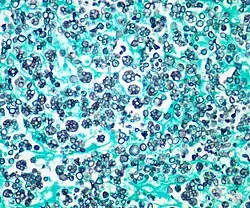

Prototheca and Helicosporidium are two unusual examples of once-algal organisms which have lost their chloroplasts and become parasitic. Prototheca infects vertebrates (including humans), and induces protothecosis; Helicosporidium infects a wide array of invertebrates.[9] Phyllosiphon is an unusual genus, consisting of branched siphonous filaments with chloroplasts. It is an endophytic parasite occurring in leaves, particularly the family Araceae.[17]

Photomicrograph (stained) of Prototheca wickerhamii infection in a human -